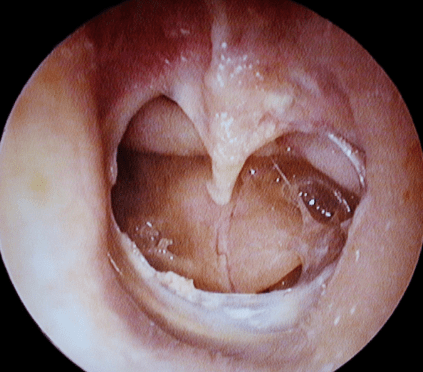

Endoscopic tympanoplasty (ET) provides minimally invasive transcanal access to the middle ear and improves middle ear visibility for the treatment of tympanic membrane (TM) perforations. However, the literature on surgical outcomes for large TM perforations is lacking and limited to small series. This study aimed to evaluate the clinical benefits of ET for large TM perforations.

This retrospective cohort study was conducted at nine tertiary referral hospitals in South Korea, where 252 patients who underwent ET as primary surgery from September 2019 to August 2021 were included. The outcome measures included the graft success rate and pre- and postoperative audiometric data.

In 239 patients, the graft success rate of ET for large or subtotal perforations was 86.2% (206 patients), while the graft failure rate was 13.8% (33 patients). The graft failure rate was directly correlated with surgical techniques, including overlay and medial or lateral underlay tympanoplasty (P=0.027). Lateral underlay tympanoplasty showed the most favorable results. Sex, laterality, etiology, site and size of perforation, operation time, and graft materials did not vary significantly between the graft success and failure groups (P>0.05). The mean air-bone gap (ABG) improved significantly in both groups (graft success group: 10.0±0.6 dB and graft failure group: 7.7±0.3 dB; P<0.001). However, the ABG improvement did not significantly differ between the groups. Analysis of covariance revealed that the postoperative 500-Hz bone conduction threshold improved after successful ET (adjusted coefficient, –11.351; 95% confidence interval, –21.491 to –1.212; P=0.028).

This study involved the largest population to date of large TM perforations treated by ET. The study findings suggest that ET is feasible and effective in treating large TM perforations.